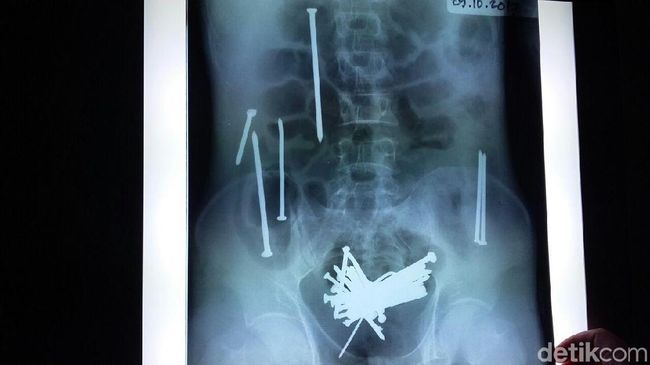

Penampakan paku dalam perut Wawan (Foto: Deden Rahadian/detikJabar).

Wawan diboyong keluarganya ke RS dr Soekardjo Tasikmalaya sebelas hari lalu setelah merasakan sakit di perutnya. Hasil rontgen memperlihatkan terdapat puluhan paku dalam perut Wawan. Sebanyak 48 paku berkarat di usus besar dan kecil Wawan berhasil dikeluarkan tim dokter. Nyawa Wawan tidak tertolong meski petugas medis berusaha maksimal memulihkannya.